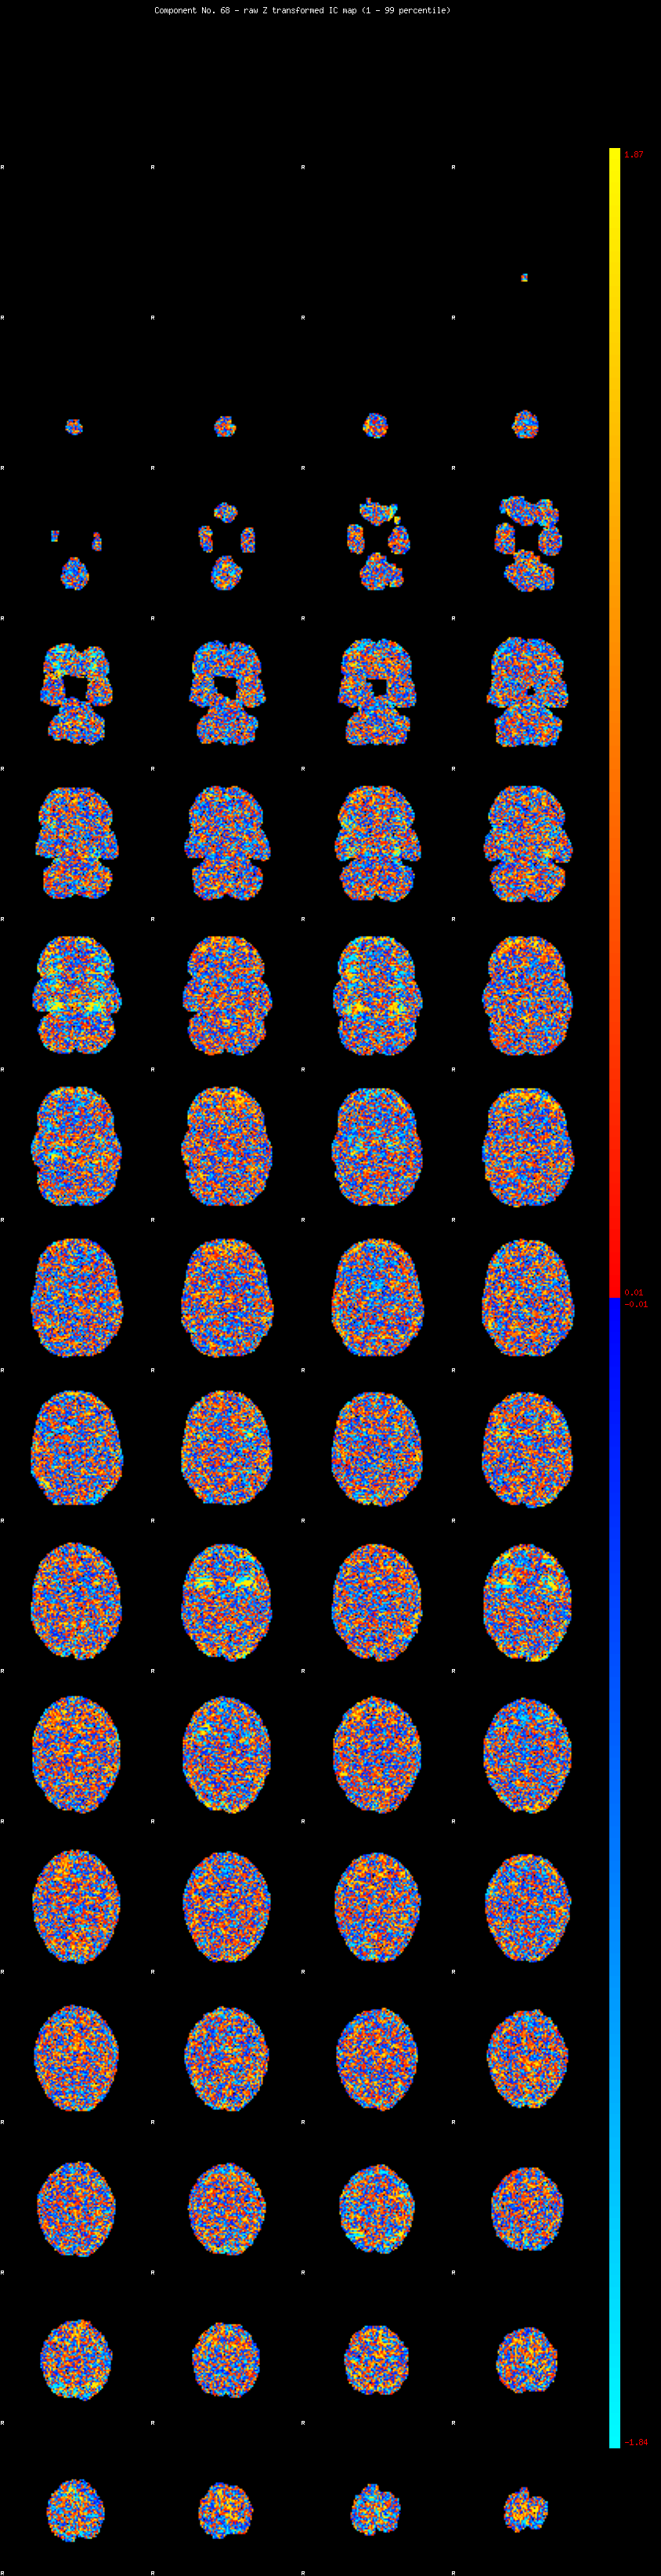

IC_68 Mixture Model fit

Means : 0.000000 2.115673 -2.155012

Vars : 1.000000 1.004480 1.117304

Prop. : 0.961651 0.020989 0.017360